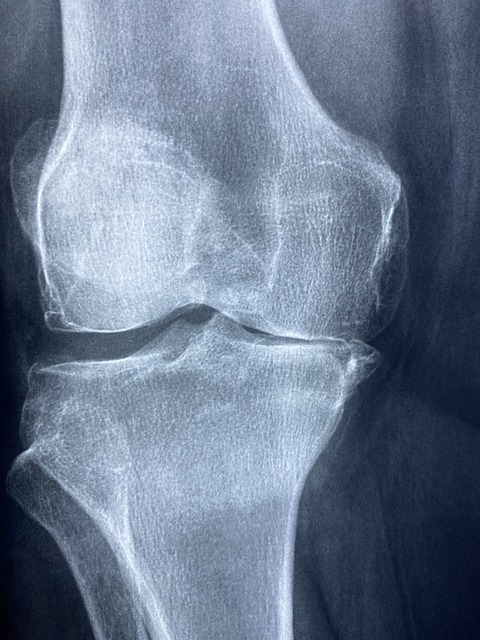

고관절 골절은 보통 엑스레이에 선명하게 나타나서 진단을 확인할 수 있습니다.

하지만 때로는 골절이 있어도, 골절이 작고 골절된 조각이 제자리에 있는 경우 정상으로 보이기도 합니다. 그래서 환자가 통증 등 증상을 계속 느끼고 설 수 없다면 작고 미세한 골절을 확인하기 위해서MRI(자기 공명영상)을 이용하기도 합니다.

CT(컴퓨터 단층 촬영)을 하기도 하지만 작은 고관절 골절을 발견하는 데에는 MRI보다 덜 정확합니다.